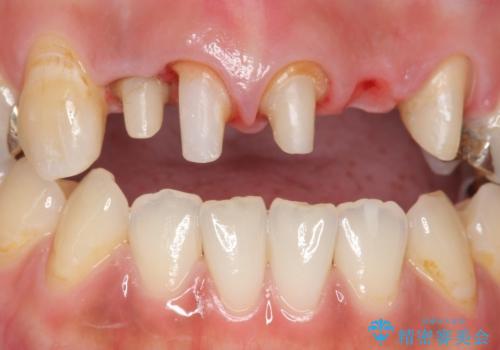

- 昔入れた被せ物と歯茎の間の隙間が気になると来院された方の症例です。

右上1、2番目の歯と左上1、2、3、番目の歯のブリッジを除去し、オールセラミッククラウンによる補綴を行うことで見た目を改善しました。